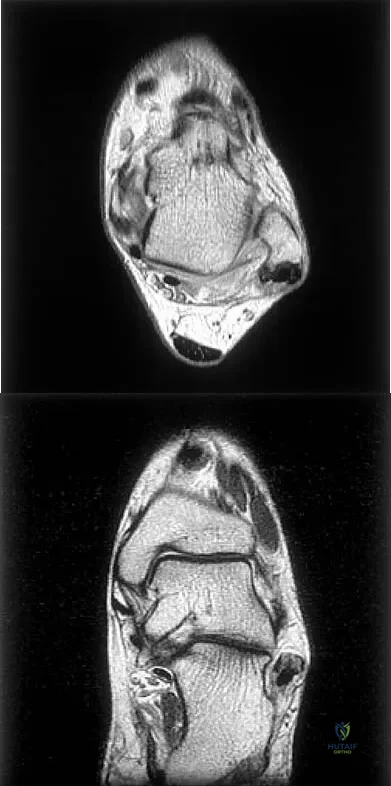

Figures 5a and 5b show axial and coronal MRI images of the left ankle of a patient with lateral ankle pain. What is the most likely diagnosis?

Explanation